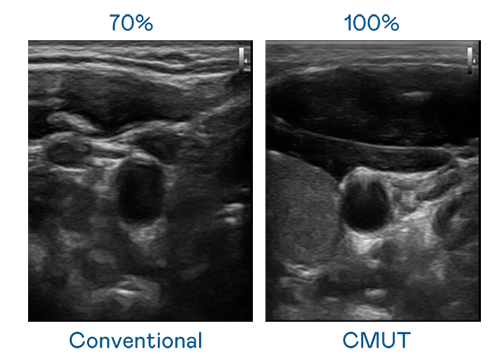

CMUT 技术是一种用电容式微机电元件来产生超音波讯号的技术。与传统 PZT 压电式技术相比,CMUT 频宽增加 30%,更宽频的超音波讯号让影像解析度大幅提升,是实现高影像品质医疗超音波扫描、促进精准医疗发展的关键技术。

超音波影像的解析度高低,首先取决于探头能发出的讯号频宽。BG真人 CMUT 可提供高清晰的超音波讯号,提供高频宽、高灵敏度、影像纹理细节更高的超音波影像,协助医护人员缩短影像判读时间及利用精准的医疗影像进行诊断。